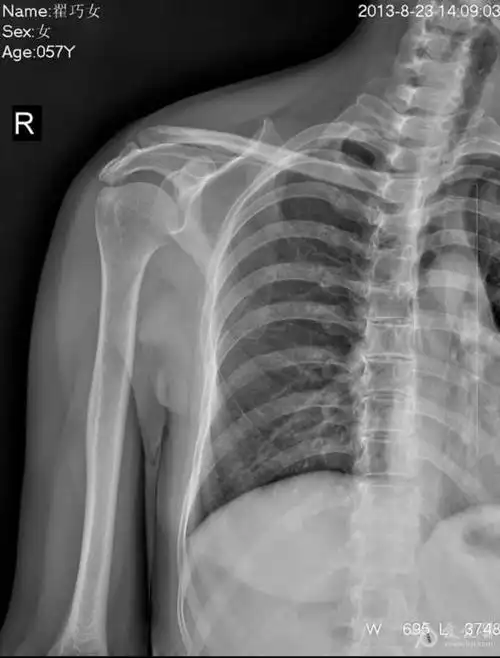

肩关节x片.这三张片子 能看出问题在哪里吗#肩关节摔伤#肩关 - 抖音

写美篇这是病人在医院拍的右肩关节x线片,相信好多人看不明白是怎么